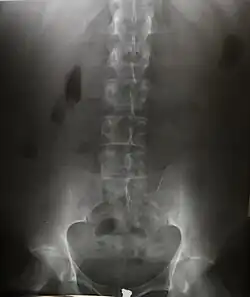

Radiografia AP da coluna lombar